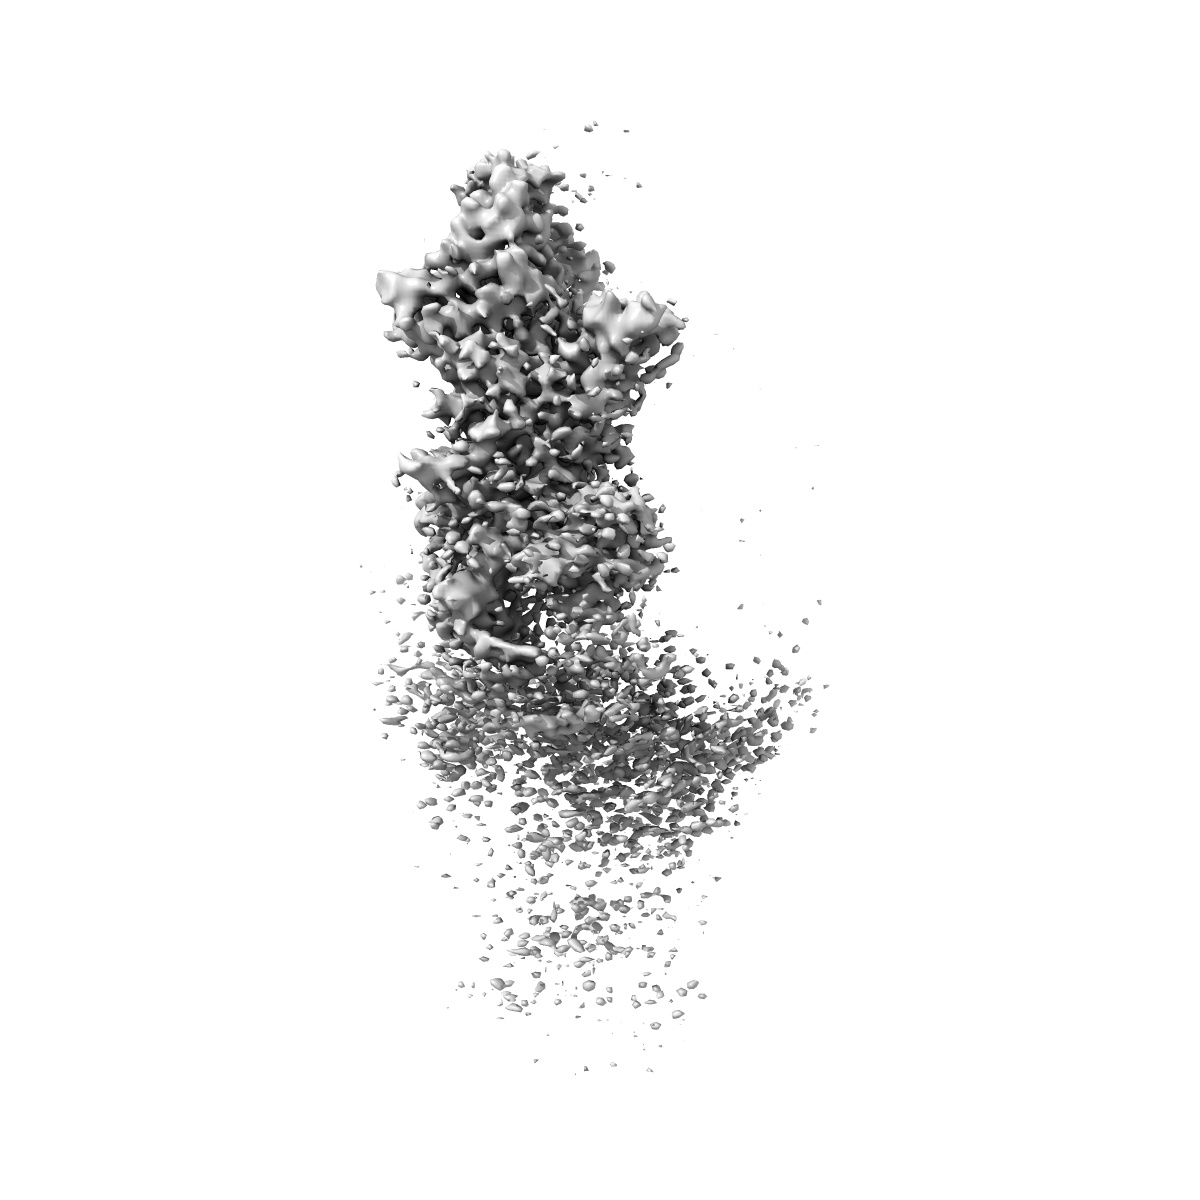

Local CryoEM structure of the SARS-CoV-2 BA.5 in complex with ORB10 Fab

Single-particle3.6 Å

Sample: SARS-CoV-2 BA.5 Spike in complex with ORB10 Fab